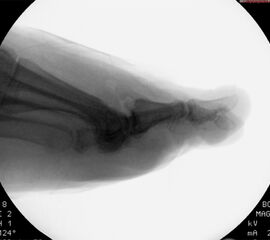

• Belastete Röntgenaufnahmen in 3 Ebenen.

Beim Hallux rigidus Stadium II beobachtet man die Ausbildung von Osteophyten dorsal, medial und lateral sowohl metatarsal als auch an der Basis des Grundphalanx bei noch ausreichender Knorpelbedeckung der plantaren Gelenkabschnitte 12. Diese führen zum Impingement, zur Einschränkung der Extension im Großzehengrundgelenk und konsekutiver Störung des Abrollverhaltens des Fußes.